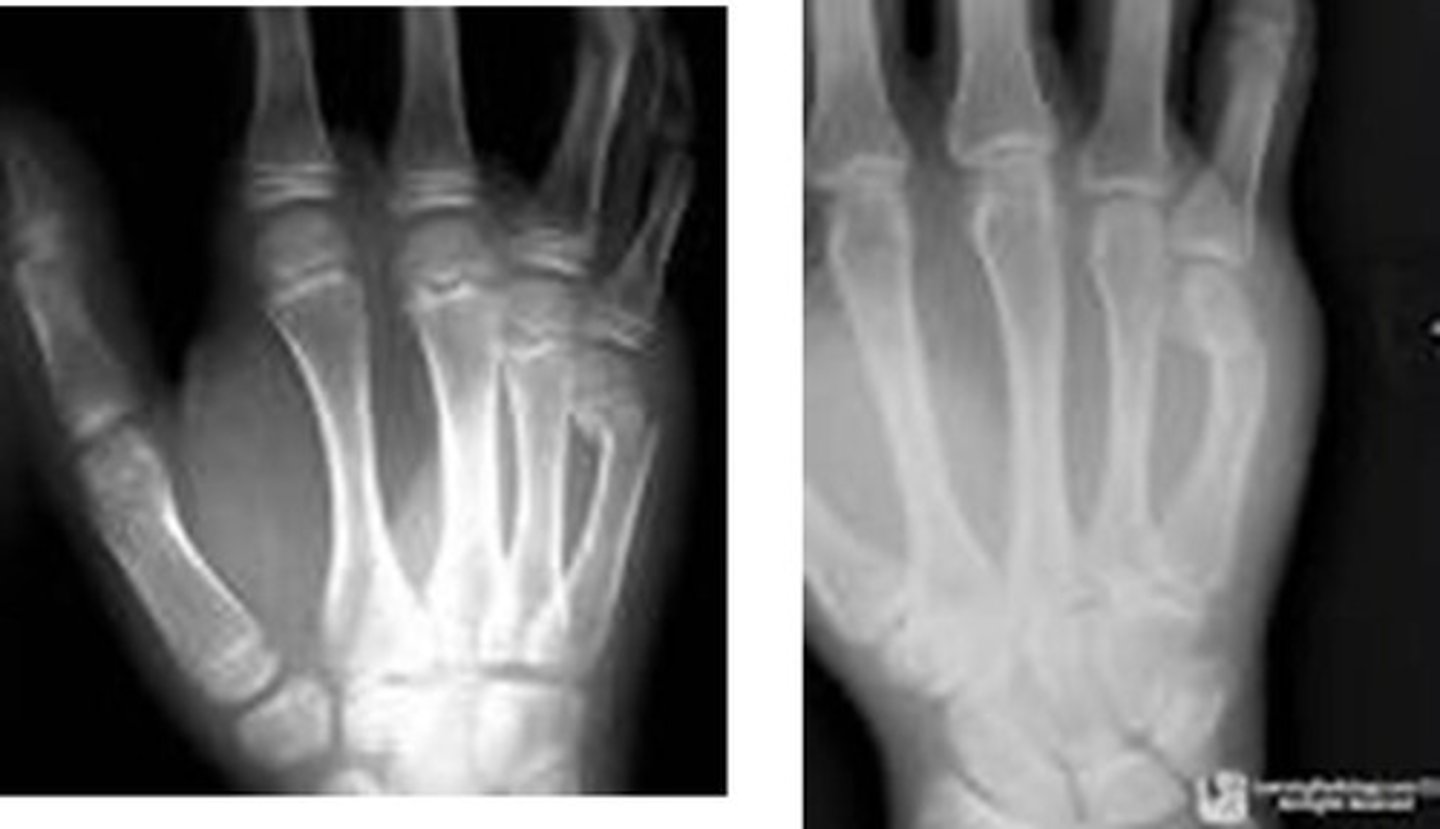

Fracture of distal fifth metacarpal

Boxer's fx